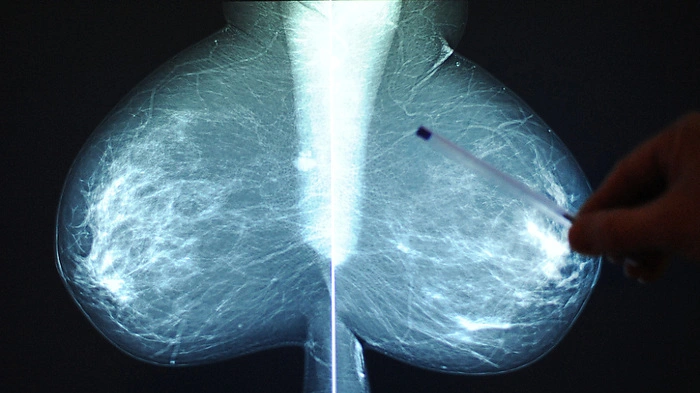

Brustkrebs häufigste Neuerkrankung bei Frauen | Brustkrebs häufigste Neuerkrankung bei Frauen

Brustkrebs häufigste Neuerkrankung bei Frauen